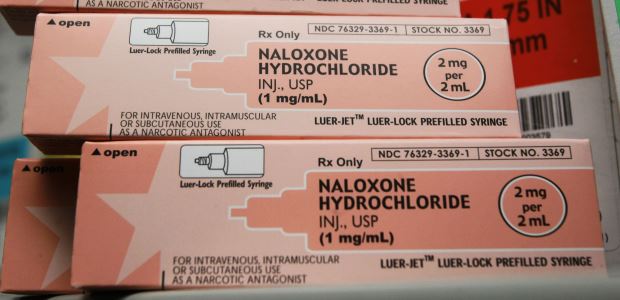

"There's nothing like MATx in the field today," said SAMHSA Principal Deputy Administrator Kana Enomoto. "It will be a significant step forward in improving timely access to medication-assisted treatment by enabling physicians and other health care practitioners to better provide effective, evidence-based, and in some cases, life-saving treatment to people with opioid use disorders."

According to the governor's office, opioid overdose deaths are now the leading cause of accidental deaths in nearly every part of Washington state, surpassing motor vehicle deaths and firearm-related deaths, and 718 people died from opioid overdoses in Washington last year.